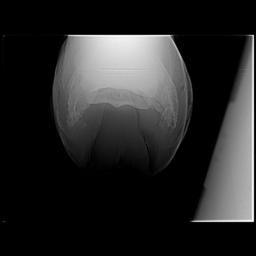

Posted on Thursday, Apr 5, 2007 - 1:11 pm: Dr O,I just read this article today after meeting with my vet and farrier yesterday regarding my horse's heel pain and I would like to get your input, if possible. I have had Remy for 6 years and have fought his low heel, long toe confirmation the whole time. In hindsight we did not do the right thing although we had the right idea. She said that if this had been managed properly for the past 6 years there would not be the damage there is now. I think the thing we missed was regular radiographs to see what was really going on. We just assumed that because he was not lame he was ok inside - the radiographs taken yesterday show that definitely was not the case. There is damage to the navicular, pedal osteitis, bone spurs and other things going on now. We have put him in 7 degree wedge pads with soft impression material. He walked off almost sound after the shoes were put on. I'm keeping a close eye on him because he can be sensitive to anything touching his sole as he has extremely thin soles. My vet said that it is important for sole growth that the frog had pressure - I had never heard that before. My vet said that it is possible that some healing can take place and he can return to regular work. She said that if the corrective shoeing doesn't work the next step would be injections - and she sounded pretty positive about the injections. We will continue to take regular xrays every 3 shoeings until we see the improvement we want. Does this sound like a good plan? I'm going to upload some radiographs that will give you an idea of what we are dealing with. I hope the thumbnails are large enough for you to view. I would greatly value any input you can give me. BTW I absolutely love this article! I'm going to print it and give it to my farrier. It's basically the same thing that he and my vet have said to me but it may have a couple extra insights. Thanks, Dawn Left front     Right front

Posted on Friday, Apr 6, 2007 - 6:36 am: Hello Dawn,I have moved your post into this new discussion. Using the radiographs as guides it would appear to me that the left could use around 7 degrees but the right a little less. This assumes the horse was standing square while radiographed. While radiographs are critical early in the assessment, because your feet do not appear to have any rotation of the coffin bone, you can assess proper balance without radiographs. This and how the foot responds to your work should be your guide to whether you have balanced these feet correctly. DrO |